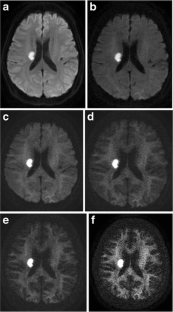

Fig. 1

Fig. 2

Fig. 3